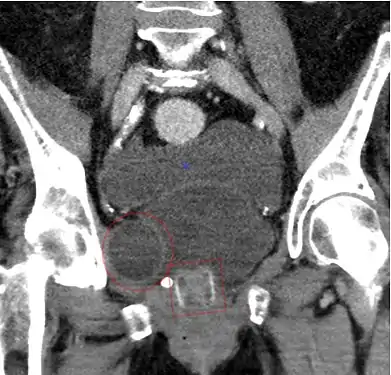

Correcting post-implantation incontinence with pressure adjustment in ZSI 375-implanted patient